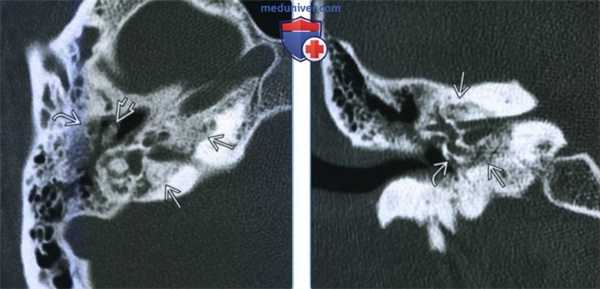

(Слева) При аксиальной КТ височной кости определяются типичные признаки запущенного сифилиса внутреннего уха. Визуализируются распространенные пермеативные изменения костей (кость, «изъеденные молью») внутреннего уха, среднего уха и сосцевидною отростка, и слуховых косточек.

(Справа) При корональной КТ височной кости у этого же пациента определяется пермеативная деминерализация слуховой капсулы с бляшкой (как при отосклерозе) на мысе улитки. Эти изменения обусловлены воспалительным резорбтивным остеитом.